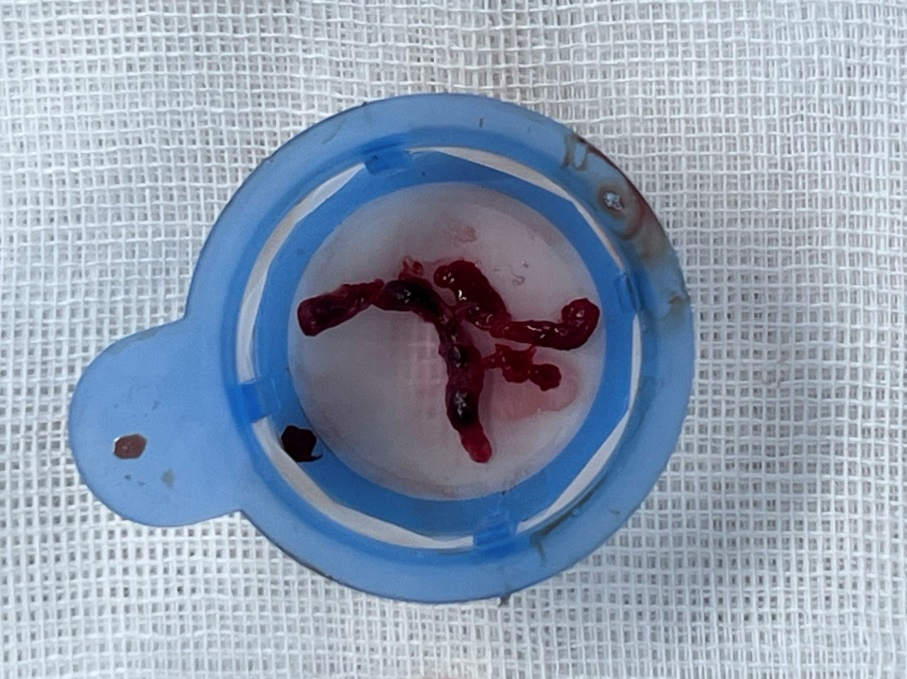

预扩后右冠远端显影,远段及PD开口处可见血栓,抽吸出约2cm长血栓1条。

再次沿PD导丝抽吸,注射器无明显回血,缓慢回拉退出抽吸导管,冲洗后未见明显血栓;但指引导管压力消失,心电正常。考虑血栓嵌顿于指引导管,尝试以注射器连接指引导管反复回抽后回血顺畅,抽出约3cm粗大血栓。

抽吸后,负压缓慢撤出抽吸导管。撤出后,将注射器和抽吸导管内血液以及指引导管回抽血液注射至过滤筛内,冲洗后观察抽吸物的形态、大小和颜色等。